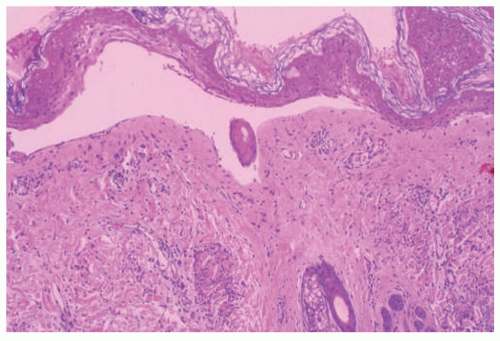

EBS is, by definition, an intraepidermal process, and intraepidermal blister formation is seen histologically (Figure 4-4).6

In the most common basal types of EBS, a split in the epidermis just below the nuclei of the basal layer keratinocytes is most characteristic (Figure 4-4), although superficial layers of the epidermis can become involved with significant trauma.6 Histologic sections for light microscopy may appear to demonstrate a subepidermal blister, as only a small portion of the basal layer keratinocyte cytoplasm may remain attached to the dermis. This is particularly true of older lesions.6 Faint remnants of basal cell keratinocyte cytoplasm are often identified at the base of the blister, and the nucleated half of the split keratinocyte may be found in the blister cavity.6 Blisters are often multiloculated, a feature most commonly seen in early lesions.6 Very early lesions may show only prominent vacuolization (sometimes referred to as “cytolysis”) of the basal layer keratinocyte cytoplasm just below the nucleus6 (Figures 4-4 and 4-5).

As the exact location of the blister may not be apparent on light microscopy alone (intraepidermal vs. subepidermal), immunohistochemical (IHC) stains, direct immunofluorescence (DIF), and electron microscopy (EM) are useful ancillary tests. While EM studies shaped our current understanding of the pathogenesis of EB,7 IHC and DIF methods have largely supplanted ultrastructural examination of routine clinical specimens.

DIF or IHC studies show keratin(s), laminin, and type IV collagen along the floor of the blister. The presence of keratin, together with laminin and type IV collage, proves that small portions of the basal layer keratinocytes are present at the floor of the blister, confirming an intraepidermal process.8